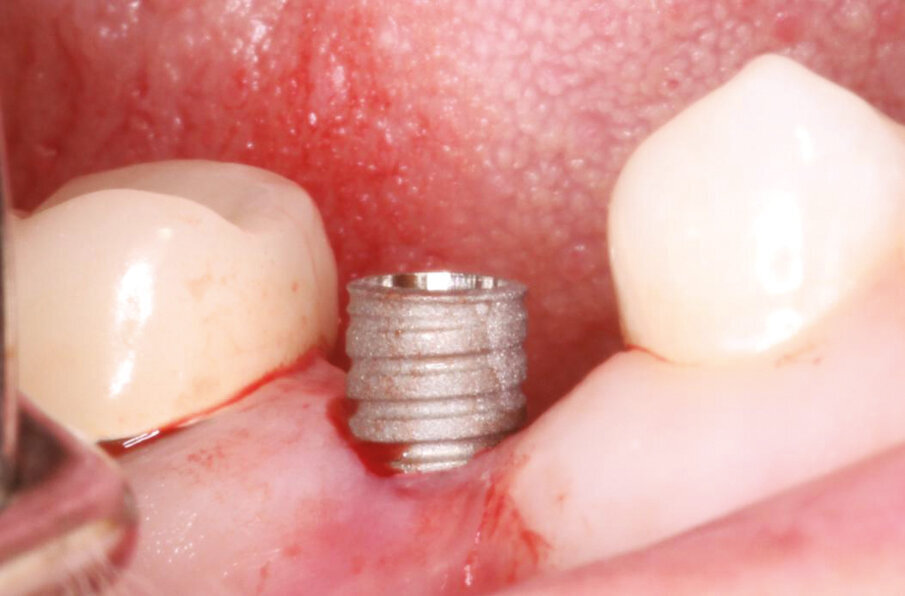

Fig.5: Axiom REG selection (4,0x10 mm).

Fig.6: Implant placed flapless in #25.

A 43-year-old female presents with missing premolar and molar upper right side (#15,16) and missing premolar upper left (#25). These teeth have been missing for 15+ years. A flapless approach was selected to minimize trauma and to facilitate quick healing. The Axiom Concept was utilized to create an emergence profile that would be difficult to detect from the natural dentition.